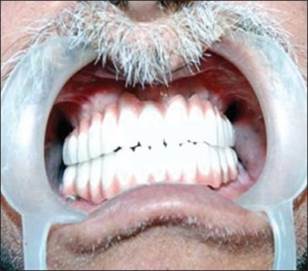

Un paciente de sexo masculino de 58 años había acudido al ala de pacientes externos de nuestro departamento, con una queja principal de falta de diente en los arcos maxilar y mandibular. El paciente quiere tener una prótesis fija ya que no estaba contento con la dentadura convencional [Figura 1] y [Figura 2] . Se registró un historial de casos adecuado para el paciente, incluido un historial médico que no era contributivo, con pruebas de laboratorio relevantes, exámenes dentales y orales. Se prepararon impresiones de diagnóstico y moldes. Se realizó un examen exhaustivo y el paciente estaba motivado para implantar prótesis. El mapeo óseo se realizó para evaluar el ancho del hueso, mediante el uso de ortopantamografía (OPG), se calculó la longitud del hueso disponible y se seleccionaron los implantes de tamaño apropiado [Figura 3]. Se preparó una plantilla quirúrgica para el maxilar y la mandíbula, y la posición de los implantes se decidió antes de la cirugía colocando un taladro en el implante.

Figura 1: Fotografía preoperatoria maxilar |

Figura 2: Fotografía preoperatoria mandibular |

Figura 8. Prótesis final en posición |

Después de la curación, se eliminaron las extensiones por mucosa y se colocaron análogos de impresión. La impresión de bandeja abierta se realizó con material de impresión elastomérico y se aflojaron los análogos de impresión. El análogo de implante se roscó al análogo de impresión en la bandeja de impresión y se vertió el molde. Se colocó el pilar sobre el yeso y se realizó el montaje. Se llevó a cabo una prueba con metal, luego se realizó la acumulación de cerámica y se fabricó la prótesis final y se verificó en la cavidad oral y se realizó la cementación final [Figura 9] . Las instrucciones de higiene oral postoperatorias se dieron al paciente y se realizó un seguimiento adecuado (Kim, Misch y Wang, 2005).

Figura 9. Prótesis final